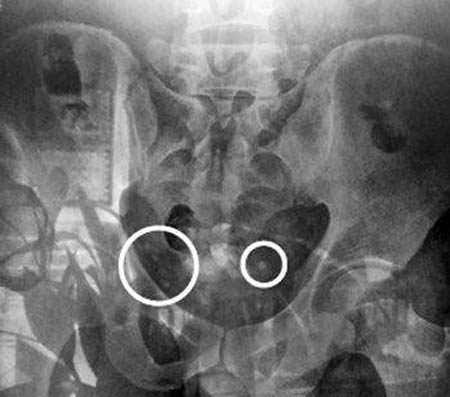

許某稱,中槍后,他的工友從工地跑出,將其送醫(yī)。在省立醫(yī)院,記者看到許某的拍片結(jié)果,其上顯示,臀部有多個(gè)圓形白點(diǎn)。